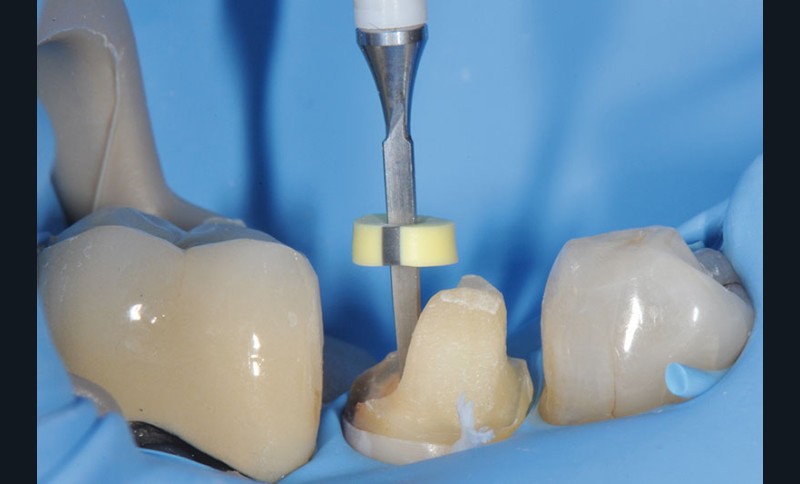

27, 28, 29. La couronne transitoire est pré-polie avec la roue spirale 3M™ Sof-lex™ beige puis polie avec la roue spirale diamantée 3M™ Sof-lex™ rose.